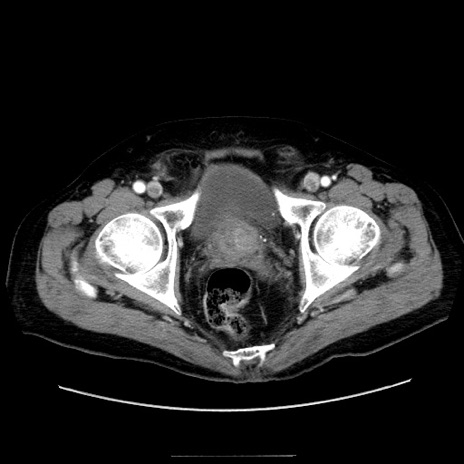

症例30(横断像)

【症例】80歳代男性

【主訴】臍周囲痛

【現病歴】約6時間前から臍下部痛が出現。次第に腹部膨隆・背部痛も生じてきたため来院。背部痛の場所は変化しない。

【既往歴】腎盂腎炎

【身体所見】意識清明、BT 36.3℃、BP  131/87mmHg、P 87bpm、SpO2 100%(RA)、臍周囲自発痛・圧痛あり、反跳痛なし、自発痛部位に一致して板状硬あり、腹部膨隆、腸雑音減弱、CVA tenderness両側陰性。

【データ】WBC 19600、CRP 0.33